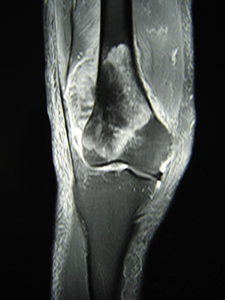

骨表面の膜(骨膜)、軟骨、筋表面の膜(筋膜)などを腫瘍の浸潤を防ぐ組織(バリアー)と見なし、このバリアーで腫瘍を包むように切除する手術です(治癒的切除)。バリアーの無い部位では腫瘍からできるだけ離し正常組織(腫瘍辺縁からの距離を計算;○cm)を含めて切除します(○cm広範切除)。安全な切除縁で腫瘍を切除することが重要であり、術後再発率はほぼ5%程度になります。当科では、MRIやCT像を基にバリアーの存在を診断し綿密に手術計画を立て、3cm以上の広範切除獲得を基本としています。

患肢温存のため、確実な腫瘍切除の後失われた組織をいかに再建するかが重要な課題になります。この目的のために、状況に応じ人工関節置換、神経・血管・骨表面に対する術中アルコール処理法、皮膚筋弁移植・遊離骨移植(腫瘍切除で皮膚に大きな欠損が生じた場合、背中やお腹、大腿部の皮膚・筋肉を血管と共に採取し欠損部を覆います;形成外科と連携)などを準備しています。

骨肉腫症例 人工関節置換術